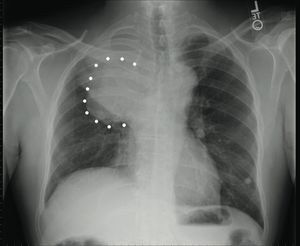

Not really. You have what is called superior vena cava compression syndrome and tenido to find Dyspnea, collateral circulation and upper body edema with cyanosis and papilledema.